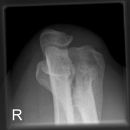

Ellenbogen ventro-dorsal (1. Ebene a.-p.)

Fraktur, Luxation, degenerative Veränderungen

Abbildungskriterien

distale Humerunsanteile: Epikondylen, Capitulum humeri

proximale Unterarmanteile: Radius-Radiusköpfchen und -hals, Ulna -Schaft, Körper, Olecranon

Ellenbogengelenk vollständig a.p. orthograd abgebildet, Gelenkspalt in Filmmitte und überlagerungsfrei.